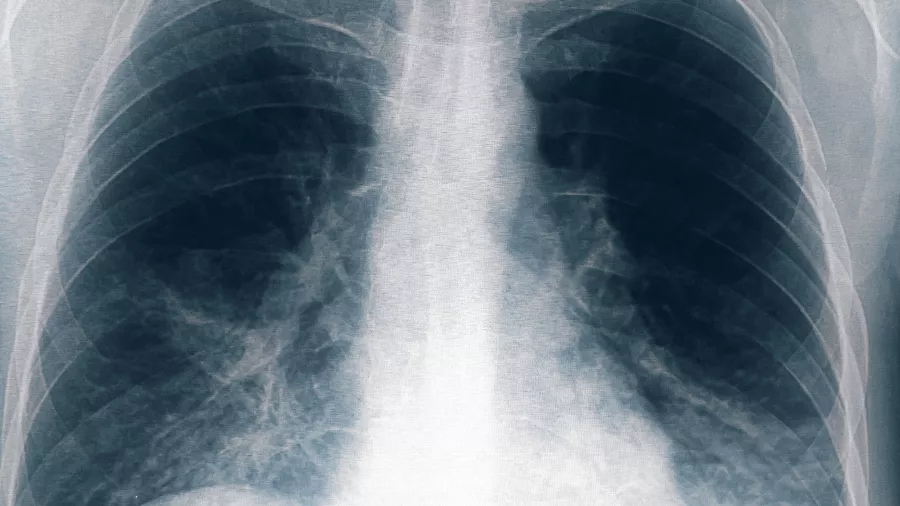

Un paciente "vinculado al conglomerado de casos de neumonía" bilateral registrados en Tucumán murió este domingo, por lo que suman cinco las víctimas fatales por esta causa, informó el Ministerio de Salud Pública provincial.

Hasta el momento se identificaron once personas afectadas por neumonía bilateral causada por Legionella, en la clínica privada Luz Médica, de las cuales cinco fallecieron.

Los primeros seis casos registrados correspondieron a cinco trabajadores de la salud y a una paciente que estaba internada en el servicio de terapia intensiva de un sanatorio privado de la ciudad de San Miguel de Tucumán, quienes iniciaron síntomas entre el 18 y el 22 de agosto, presentando fiebre, mialgia, dolor abdominal y disnea.